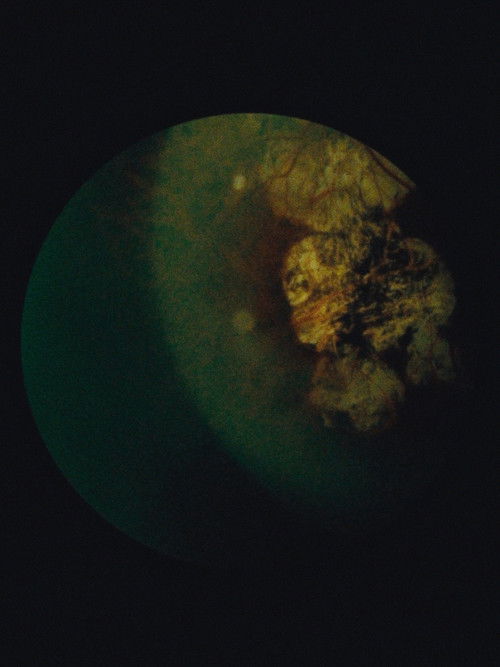

Immaculate Generations no. 1